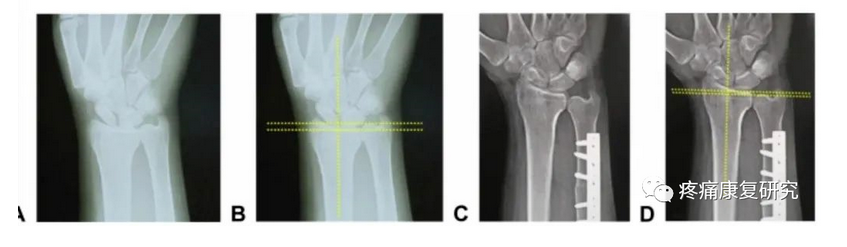

尺骨撞击综合征患者行尺骨短缩截骨术术前术后X线片

目前 USO 截骨部位有尺骨干截骨和干骺端截骨,钢板安置部位有掌侧和背侧,截骨方式有徒手截骨和专用工具引导下截骨,截骨形状有横形、斜形、梯形等,其中徒手截骨和横行截骨因操作简便而应用较广。